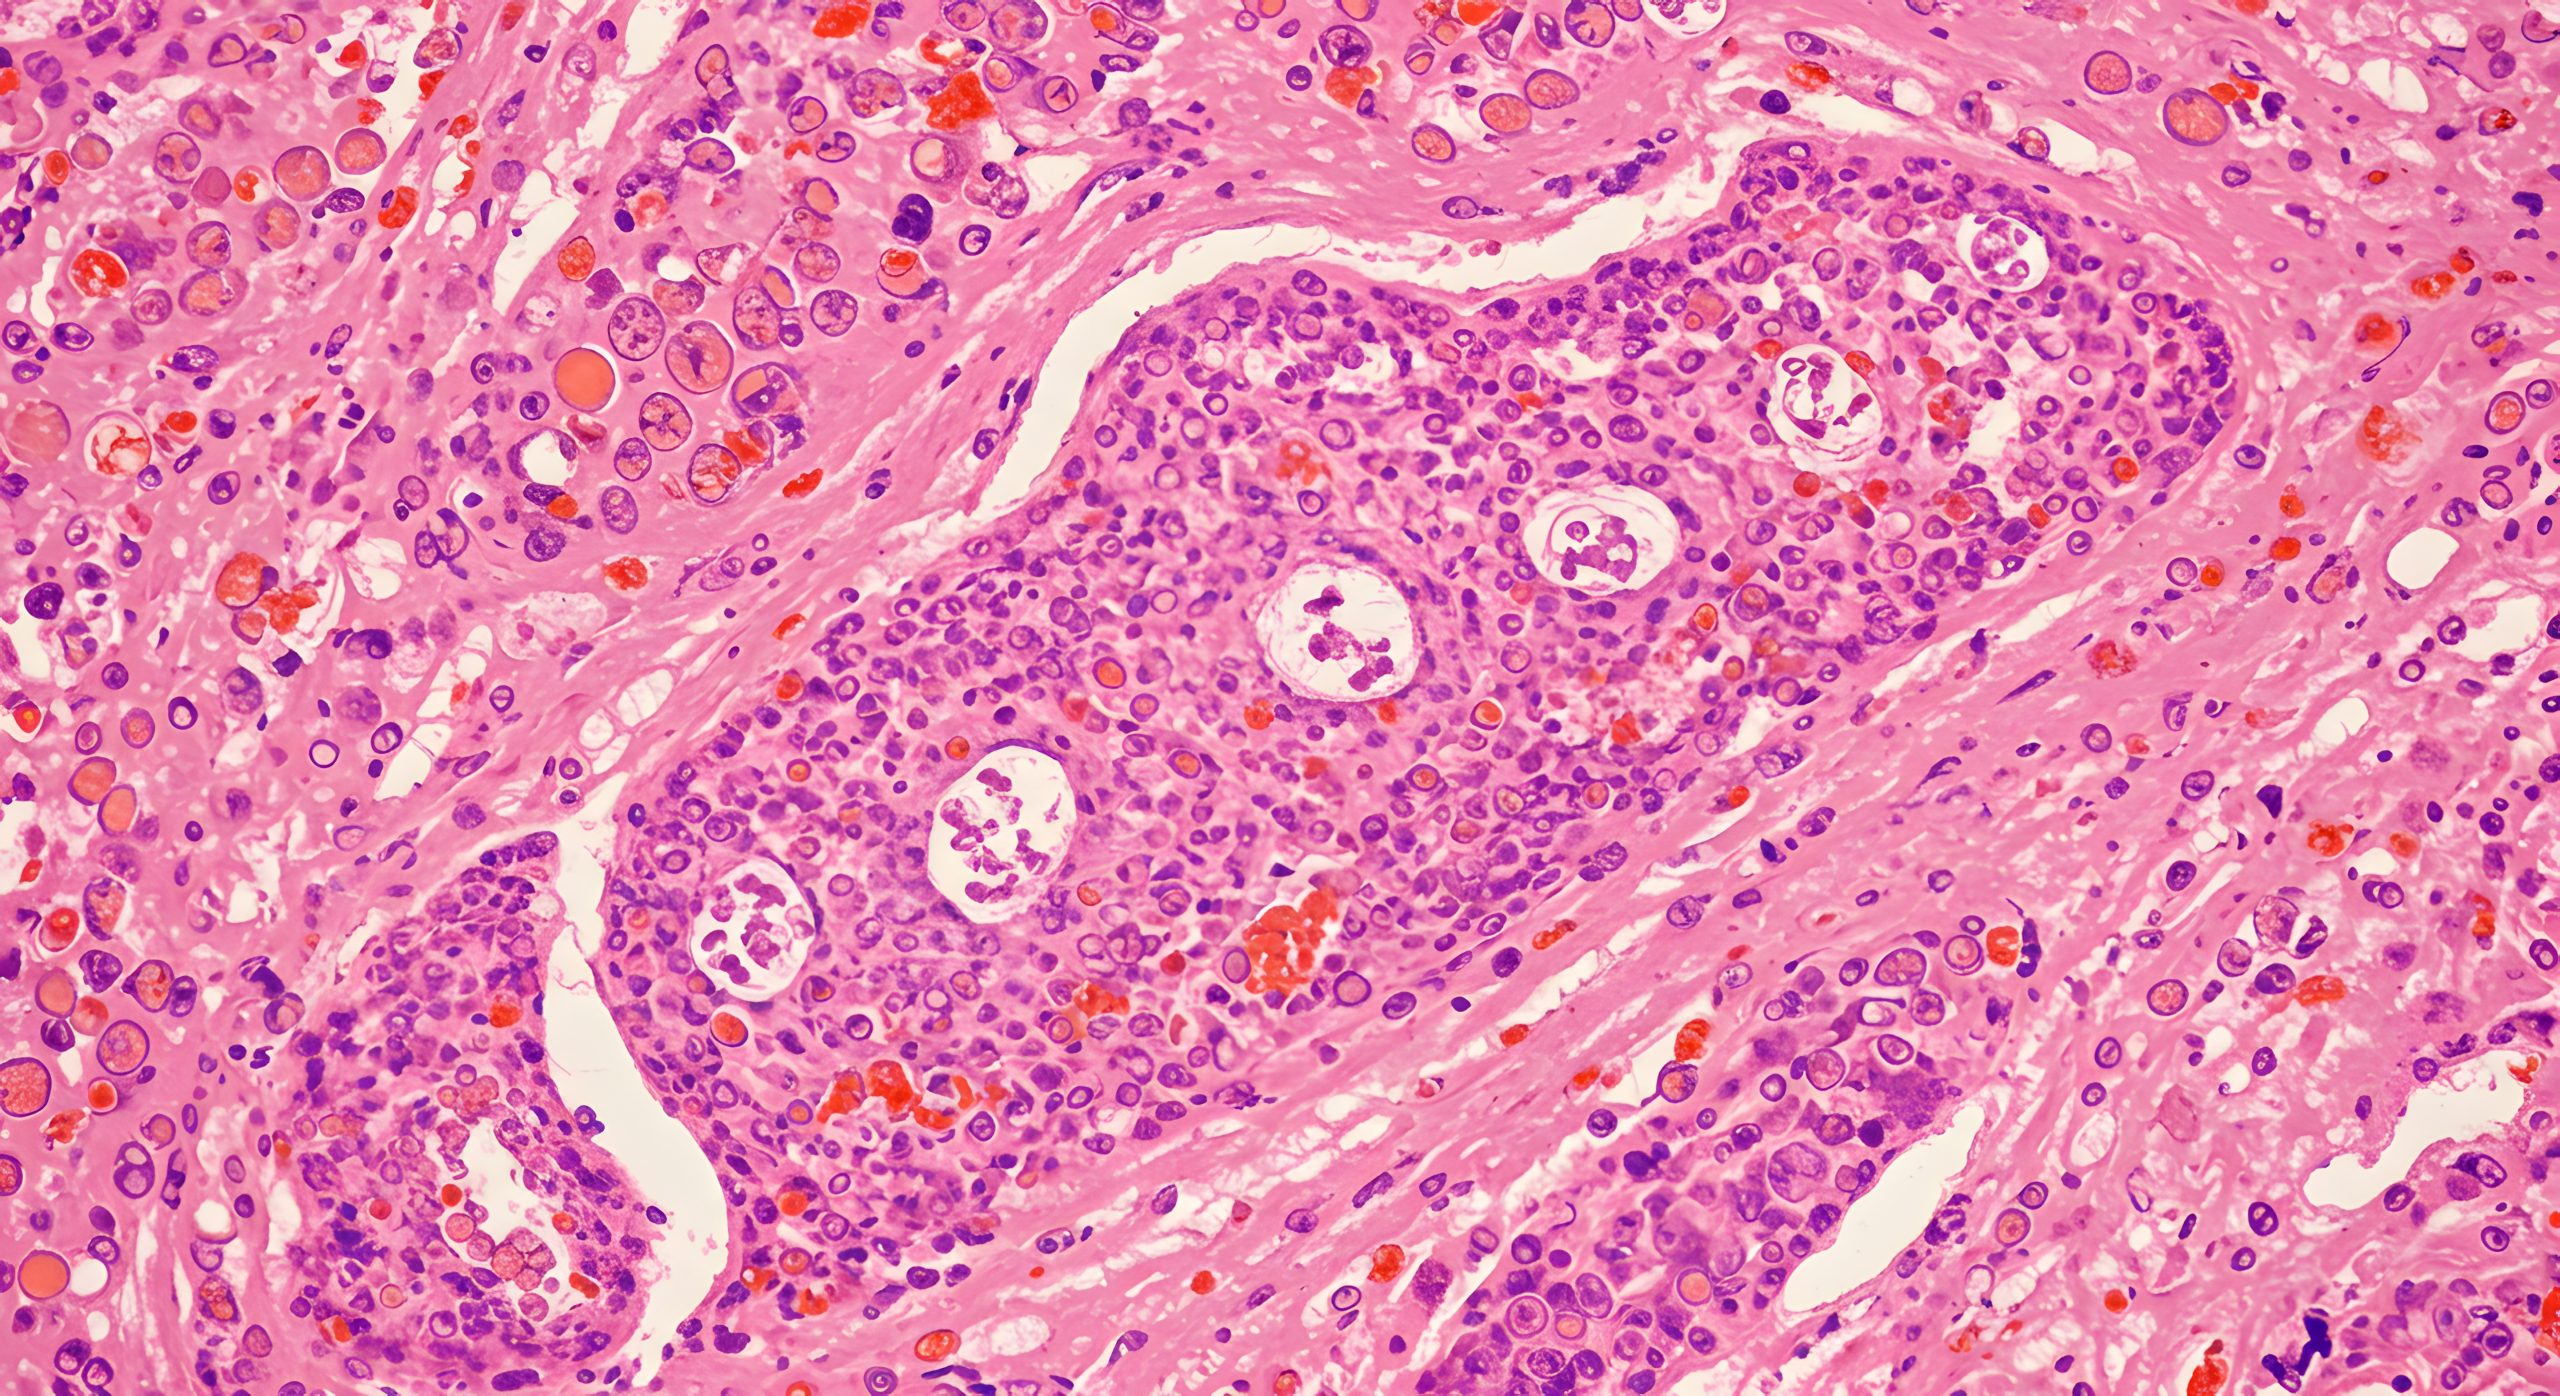

Auch bei Verdacht auf bösartige Erkrankungen (bsp. Mammakarzinom) oder zur Nachsorge nach einer Therapie bietet die Brustsprechstunde einen geschützten Rahmen für Diagnostik, Aufklärung und Begleitung. Durch den Einsatz moderner Ultraschalltechniken und – falls notwendig – gezielter Gewebeentnahmen (Stanzbiopsien) kann eine sichere Abklärung erfolgen.

• Ultraschall-geführte Stanzbiopsien (Gewebeprobe) bei unklaren Befunden